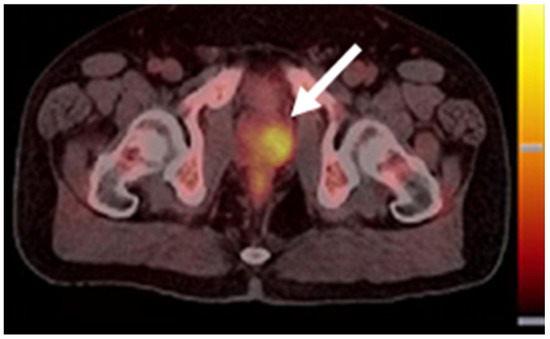

Figure 4. A [18F]fluciclovine PET/CT image of PCa (white arrow). This research was originally published in the Journal of Nuclear Medicine (JNM) [36].

The diagnostic performance of [18F]FACBC was widely assessed after the FDA’s approval. The reported overall detection rate for [18F]FACBC ranged from 40% to 80%, depending on the size of patient cohorts, and like [11C]choline, its detection rate positively correlated with patients’ PSA levels(see Table 2 [37,38,39,40,41,42,43]). In a study investigating BCR patients with very low PSA levels (≤0.3 ng/mL), the detection rates were 43.8% for patients with PSA level below 0.1 ng/mL, increasing up to 65.2% for patients with PSA between 0.2 and 0.3 ng/mL [44]. In patients with BCR, an [18F]FACBC PET/CT scan led to mainly major changes in clinical management for 40% of patients [45].